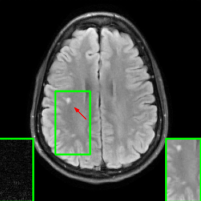

Figure 1 illustrates reconstructed images from the instabilities and the generalization challenges considered in this paper.

| PSNR = 30.8 dB | PSNR = 23.21 dB | PSNR = 22.18 dB |

![]() |

| (a) | (b) | (c) |

| PSNR = 24.15 dB | PSNR = 27.26 dB |

| (d) | (e) |